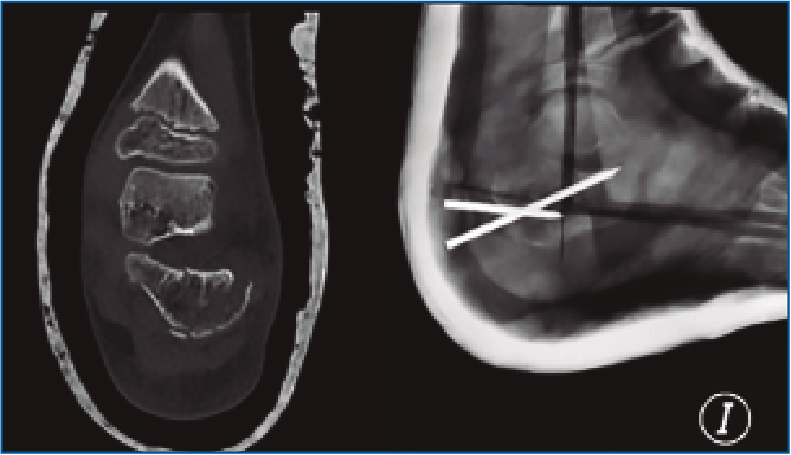

En nuestra serie, solo se aplicó reducción cerrada y fijación percutánea con agujas de Kirschner (AK) en un paciente de 7 años (Figura 2). La técnica quirúrgica tiene como objetivo introducir una AK a través de la apófisis y fisis para reducir la altura y longitud del calcáneo. Otra AK se introduce en el fragmento con la faceta posterior desplazada con el propósito de elevarla. Si fuera necesario, se puede introducir otra AK a través del córtex lateral para elevar los restos deprimidos de la articulación subtalar.

Figura 2. Fractura tipo Sanders III en un paciente de 7 años tras politraumatismo. Reducción y fijación mediante agujas de kirschner.